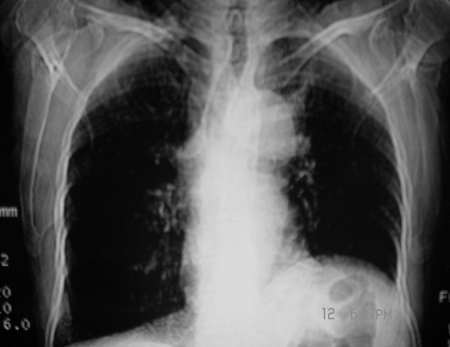

女,80岁。因咳嗽,声音嘶哑1月

1、左上纵隔旁型肺癌;

2、左侧横膈抬高,结合临床有声音嘶哑,考虑侵犯纵隔可能;

3、两肺间质纤维化;

4、右肺中叶炎症;

5、肝ⅷ段巨大囊肿。

临床表现:老年女,80岁。以咳嗽,声音嘶哑1月为主诉。

病灶和主动脉弓是宽基底相连,但与主动脉弓壁之间的脂肪间隙清晰可见;肺窗示病灶边缘有不规则毛刺样;左肺叶段肺气肿;左侧横膈升高。右肺中叶炎变;结合病史考虑纵隔型肺癌可能性大。其他的难说!

左上肺纵隔旁可见一形态略不规整的软组织肿块,与主动脉弓壁之间的脂肪间隙清晰,肺窗示病灶边缘有不规则毛刺样改变,右肺中叶炎症。综合病史考虑纵隔型肺癌。